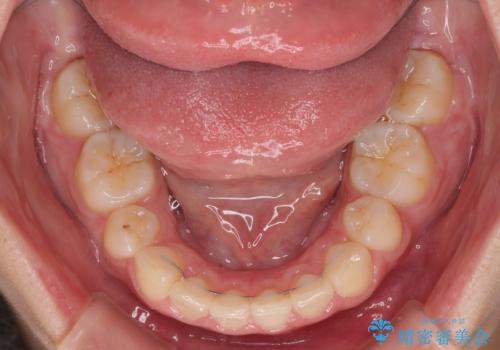

- 飛び出した上顎前歯と、閉じにくい唇、口元の突出した印象の横顔を気にして来院された患者様です。

骨格的な上顎前突であり、上下前歯の前後的な距離が大きいため、上顎は左右第一小臼歯を、下顎は左右第二小臼歯をそれぞれ2本抜歯することで前歯が接触するようにし、さらには奥歯の咬み合わせも、より理想的な状態へ近づけていくこととしました。